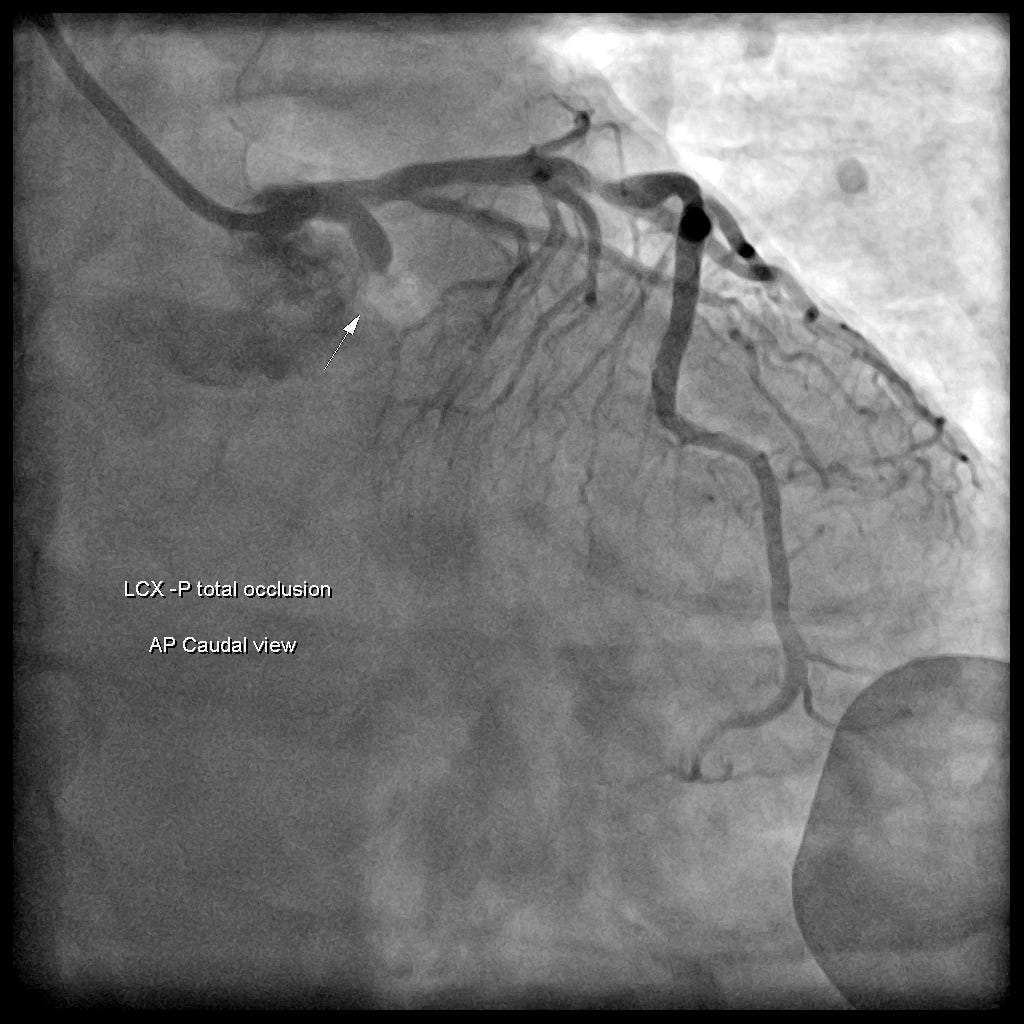

當然病患在種種急診提供的Post.wall MI證據下,啟動了緊急心導管。

看到Isolated Post.wall MI➡比較常見是LCx occlusion而不是RCA occlusion➡通常這些case(isolated Post.wall MI)的PL branch無法提供足夠的血液避免缺血(如果可以提供足夠血液,那麼就不會出現isolated Post.wall MI了)。

CAG finding:LCx-P total occlsuion